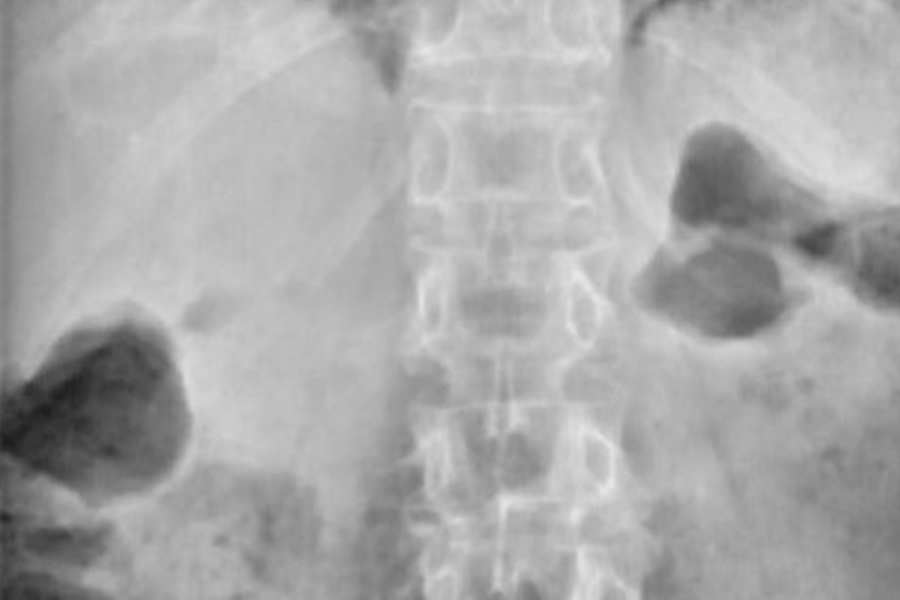

Caso clínico: endoscopia de columna multinivel L4L5 y L5S1

Los síntomas que presentaba el paciente eran dolores acentuados en las piernas, claudicación a la marcha y calambres y hormigueos en las piernas.

Durante la intervención quirúrgica, se abordarán los dos niveles mediante la técnica de endoscopia de columna.